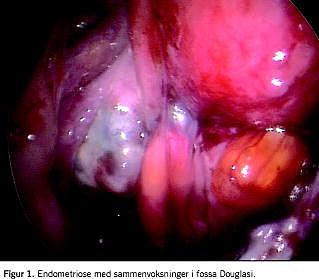

I Tabel 2 kan man se, at antallet af patienter med rektovaginal endometriose blev mere end tredoblet fra 2000 til 2005. I begyndelsen var det kun omkring 30%, men i 2005 gjaldt det 66% af kvinderne med rektovaginal endometriose, som blev behandlet på de to specialistcentre. Figur 1 viser et tilfælde med svær endometriose i fossa Douglasi.